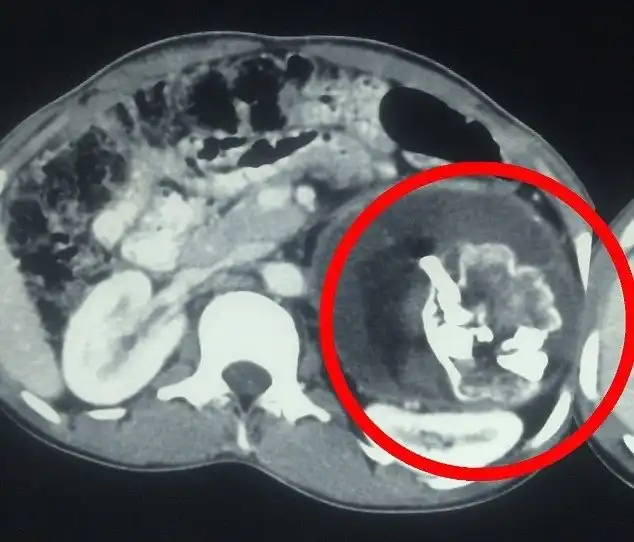

18-летний Нарендра Кумар с детства страдал всевозможными недомоганиями и потерей веса. Его родители были вынуждены обратиться к врачам, когда его состояние стало совсем скверным. Причиной тому оказался близнец-паразит с зубами и волосами, прятавшийся внутри пацана.